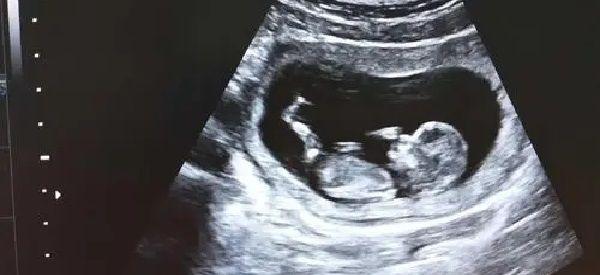

上个周去医院做了NT检查,检查的结果是胎头在左边,我在网上查了孕期胎头在左边是什么意思?在网上看到说胎头位置能分辨男女,虽然有点难以置信,但我还是想在这里问问你做NT检查后胎头在左边是男还女?

孕期根据胎儿头部位置判断性别,这种方法并不科学,通常情况下胎儿的性别早在受精卵形成的那一刻就已经注定了,然后在孕中期左右,由于胎儿的体积偏小,就会在子宫内频繁的变胎位,这个时候胎头也就会发生改变,当然不管是男胎儿还是女胎儿,都会在孕期发生这种现象,所以用这种方法并不能分辨胎儿性别。

昨天13周去做NT后竟然听说宝宝头骨形状可以准备判断出男女,那么你知道Nt检查后显示胎儿头颅形状可以看男女这有科学依据吗?

通过NT检查后看胎儿头骨形状判断男女,这种方法并没有科学依据,不管是男性胎儿还是女性胎儿,在孕期额头的变化并没有规律可言,孕期做NT检查主要是排除胎儿畸形的。建议孕妇们不要想的太多了,目前而言,孕期鉴别胎儿性别最科学的方法是通过做B超或是彩超检查,但做这两项检查后,通常情况下医生并不会告诉孕妇胎儿目前的性别。

NT可以测出胎儿是否发育畸形